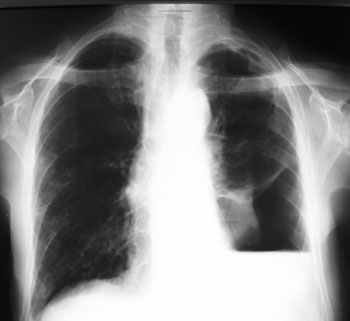

Ein 53-jähriger Patient verspürt seit gestern bereits bei leichter Anstrengung Atemnot.

Schon seit einigen Monaten fühlt sich der Mann müde und hat einige Kilos an Gewicht verloren. Sein Thorax-Bild sieht folgendermassen aus:

Thorax pa

Wie beurteilen Sie das Bild?